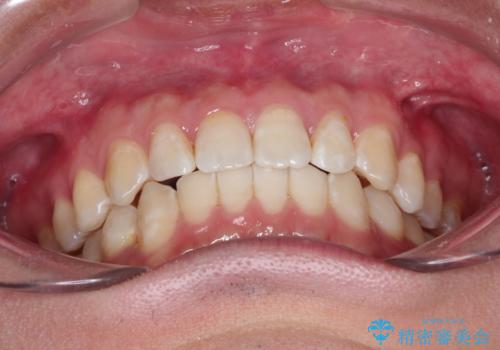

- 前歯がガタガタ、下の犬歯が飛び出ているのを主訴に来院されました。

下の奥歯を後方へ移動させてスペースを確保して、前歯を並べる計画としました。

目立たない装置をご希望されたので、インビザラインにて矯正治療を行いました。

使用時間を守っていただけたので、比較的スムーズに矯正を終了することができました。